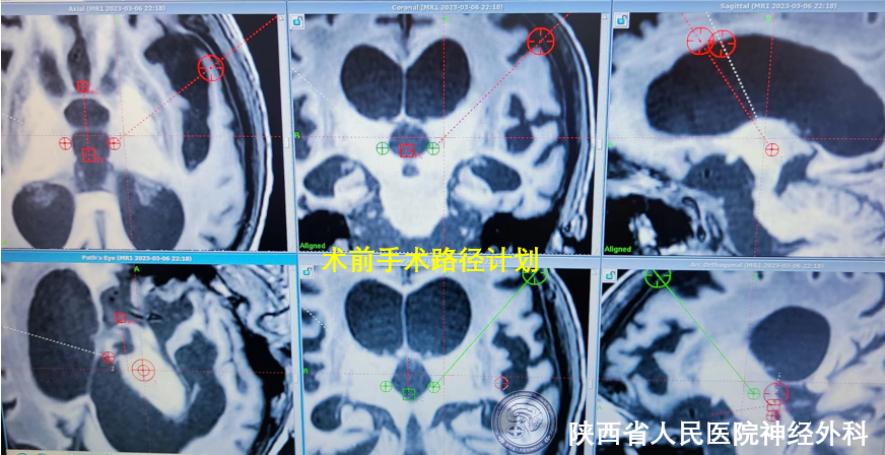

患者车祸外伤后意识不清7月余,大脑缺血缺氧损伤,伤后长期呈昏迷状态,对症康复保守治疗作用不佳,其意识水平长期维持在植物状态,CRS-R评分8分,自发睁眼,存在睡眠-觉醒周期,但无意识内容。患者家属促醒治疗意愿强烈,经过神经外科功能团队系统化的专业评估,完善多次昏迷恢复量表、长时程视频脑电图、多次术前CT及磁共振不同序列等评估,患者接受脑深部电刺激促醒治疗手术指征明确,术前经过严格的手术路径设计,手术靶点标定为丘脑中央中核-束旁核复合体(cm-pf),由于该靶点位置较深,是一个相互传递丘脑皮质信息的丘脑内束,其复合体直径仅约10mm,并且穿刺需避开脑沟脑室,为保证穿刺靶点的精确性,患者于手术当日清晨再次安装Leksell立体定向头架扫描颅脑CT,融合CT与术前磁共振数据并修正靶点坐标,术中精确设计入颅通道后精准定位穿刺靶点,双侧电极及刺激器植入顺利;患者术后再次复查颅脑CT并与术前磁共振影像融合,确认电极精准位置精准;目前患者反应良好,拟于近期开机进行规范化的术后程控促醒治疗。